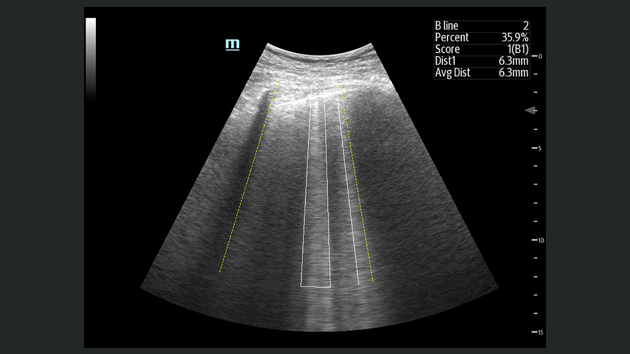

L'├®chographe TE9 a ├®t├® con?u pour faciliter les soins et ├®tendre les capacit├®s d'imagerie pour lŌĆÖanesth├®sie, les urgences et les soins intensifs. Gr?ce ├Ā ses fonctions avanc├®es, son grand ├®cran tactile et sa technologie d'imagerie sup├®rieure, l'├®chographe TE9 permet d'am├®liorer l'efficacit├® clinique et dŌĆÖassurer un diagnostic en toute confiance. Gr?ce ├Ā des outils dŌĆÖacquisition et de calculs automatiques, les soignants peuvent obtenir des mesures rapides et reproductibles dans le cadre d'examens et proc├®dures fiables, m├¬me dans des environnements o├╣ le rythme est soutenu.